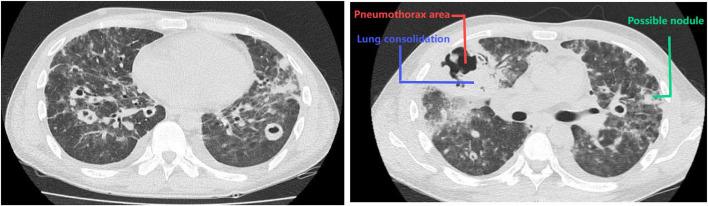

We present a patient diagnosed with nephrotic syndrome and disseminated Nocardia sepsis who was successfully treated with a combination of antibiotics and supportive care, including extracorporeal membrane oxygenation (ECMO). In addition, we performed a literature review of similar cases to provide valuable guidance for future management of cases. The present case demonstrates that ECMO should be included in the comprehensive treatment strategy for disseminated Nocardia sepsis in a patient with nephrotic syndrome. In the present case, Nocardia infection occurred during prolonged steroid and immunosuppressive therapy for nephrotic syndrome, accompanied by septic shock, respiratory failure, multiple organ dysfunction, ventilator-associated pneumonia, catheter-associated bloodstream infection with multidrug-resistant bacteria potentially due to ECMO, and hemopneumothorax. The patient received invasive ventilation, ECMO, hemoperfusion for cytokine removal, and thoracoscopic drainage, which effectively eliminated symptoms to achieve complete recovery. ECMO was applied as a life-support intervention to manage severe respiratory failure and septic shock secondary to disseminated Nocardia sepsis. This approach provides adequate infection control and stabilization of organ functions. The findings suggested that a combination of 2 to 3 antibiotics, including trimethoprim-sulfamethoxazole, imipenem, and linezolid, alleviated the severe Nocardia infections. Therefore, ECMO may serve as a supportive intervention in severe infections but requires careful risk-benefit analysis. In such cases, strict monitoring is required to prevent the occurrence of bloodstream infections, particularly multidrug-resistant bacteria, during ECMO cannulas or circuits.